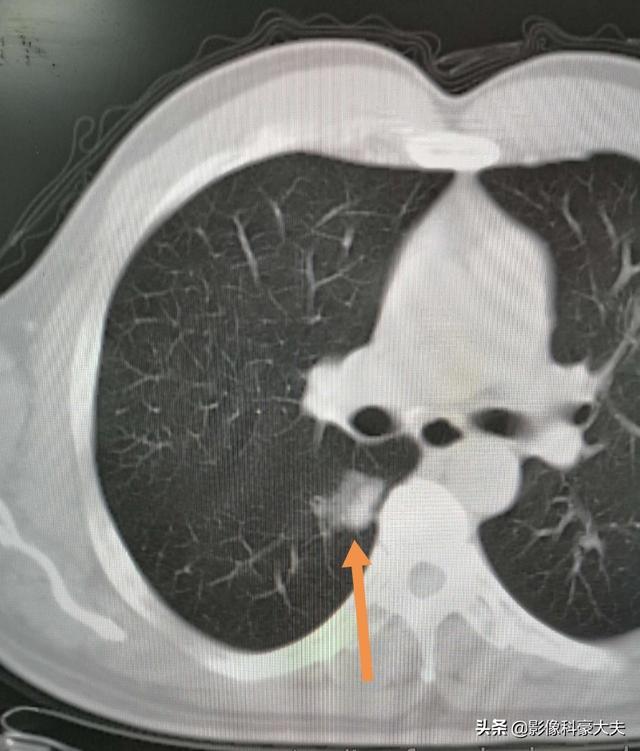

La récupération après une chirurgie du nodule pulmonaire est également liée au type de chirurgie pratiquée

La résection sous-lobaire (c'est-à-dire la résection segmentaire ou la résection en coin) a moins d'impact sur la fonction pulmonaire parce que moins de tissu pulmonaire est enlevé et qu'il reste plus de tissu pulmonaire normal. Si une lobectomie est pratiquée parce qu'une plus grande quantité de tissu pulmonaire est enlevée, il reste relativement moins de tissu pulmonaire normal, ce qui a un impact plus important sur la fonction pulmonaire et est plus susceptible de provoquer une gêne thoracique. Les photos suivantes montrent les poumons après deux résections différentes. La photo du haut montre la lobectomie du nodule pulmonaire inférieur droit, et vous pouvez voir que le poumon droit est significativement plus petit après l'opération. L'image du bas montre une résection sous-lobaire du nodule pulmonaire inférieur gauche, et vous pouvez voir que le poumon gauche conserve un volume plus important après l'opération.